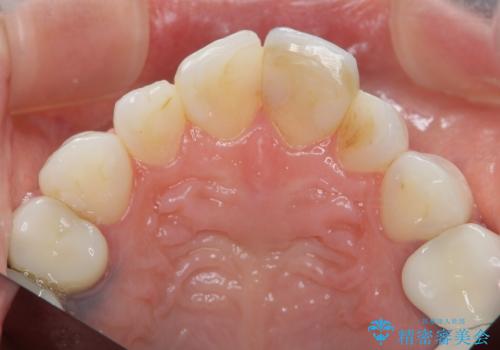

ラミネートベニヤの破折 ジルコニアクラウンによるやり替え

- 欠けてしまった前歯のラミネートベニヤと見た目の改善を求めて来院されました。

歯の大きさの不揃いと、虫歯の再発を認めたためラミネートのやりかえではなく一挙に問題の解決のできるジルコニアクラウンでの治療を計画します。

歯の大きさの不揃いが改善されただけでなく、色調もよくなり審美性をしっかりと改善することができました。